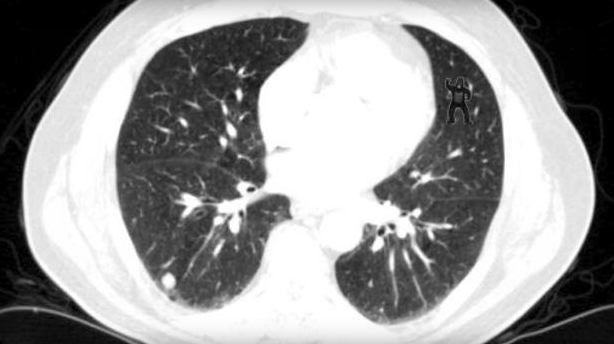

This image was presented to radiologists after they were told to look for abnormalities including lung nodules. Do you see the abnormality? Don’t worry…you don’t need to be an expert at reading CTs…it should be obvious!

24 radiologists examined this image and 20 were not able to identify the gorilla in the upper right corner! 20/24 didn’t see it! that’s unbelievable. They’re so focused on looking for other things that they glazed right over it. Using eye tracking technology, the reserachers were able to show that impressively 12 looked directly at the gorilla but still they didn’t see it!